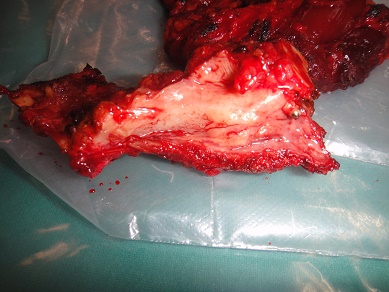

32 YEARS OLD MALE SUFFERING FROM RIGHT LOWER GINGIVO BUCCAL MUCOSA CARCINOMA INVOLVING RIGHT RETROMOLAR TRIGONE.PATIENT HAS ACTIVE PULMONARY TUBERCULOSIS.RIGHT RADICAL NECK DISSECTION WITH RIGHT DISTAL MANDIBULECTOMY WITH RIGHT LOWER ALVEOLECTOMY WITH RIGHT PECTORALIS MAJOR MYOCUTANEOUS FLAPE DONE.